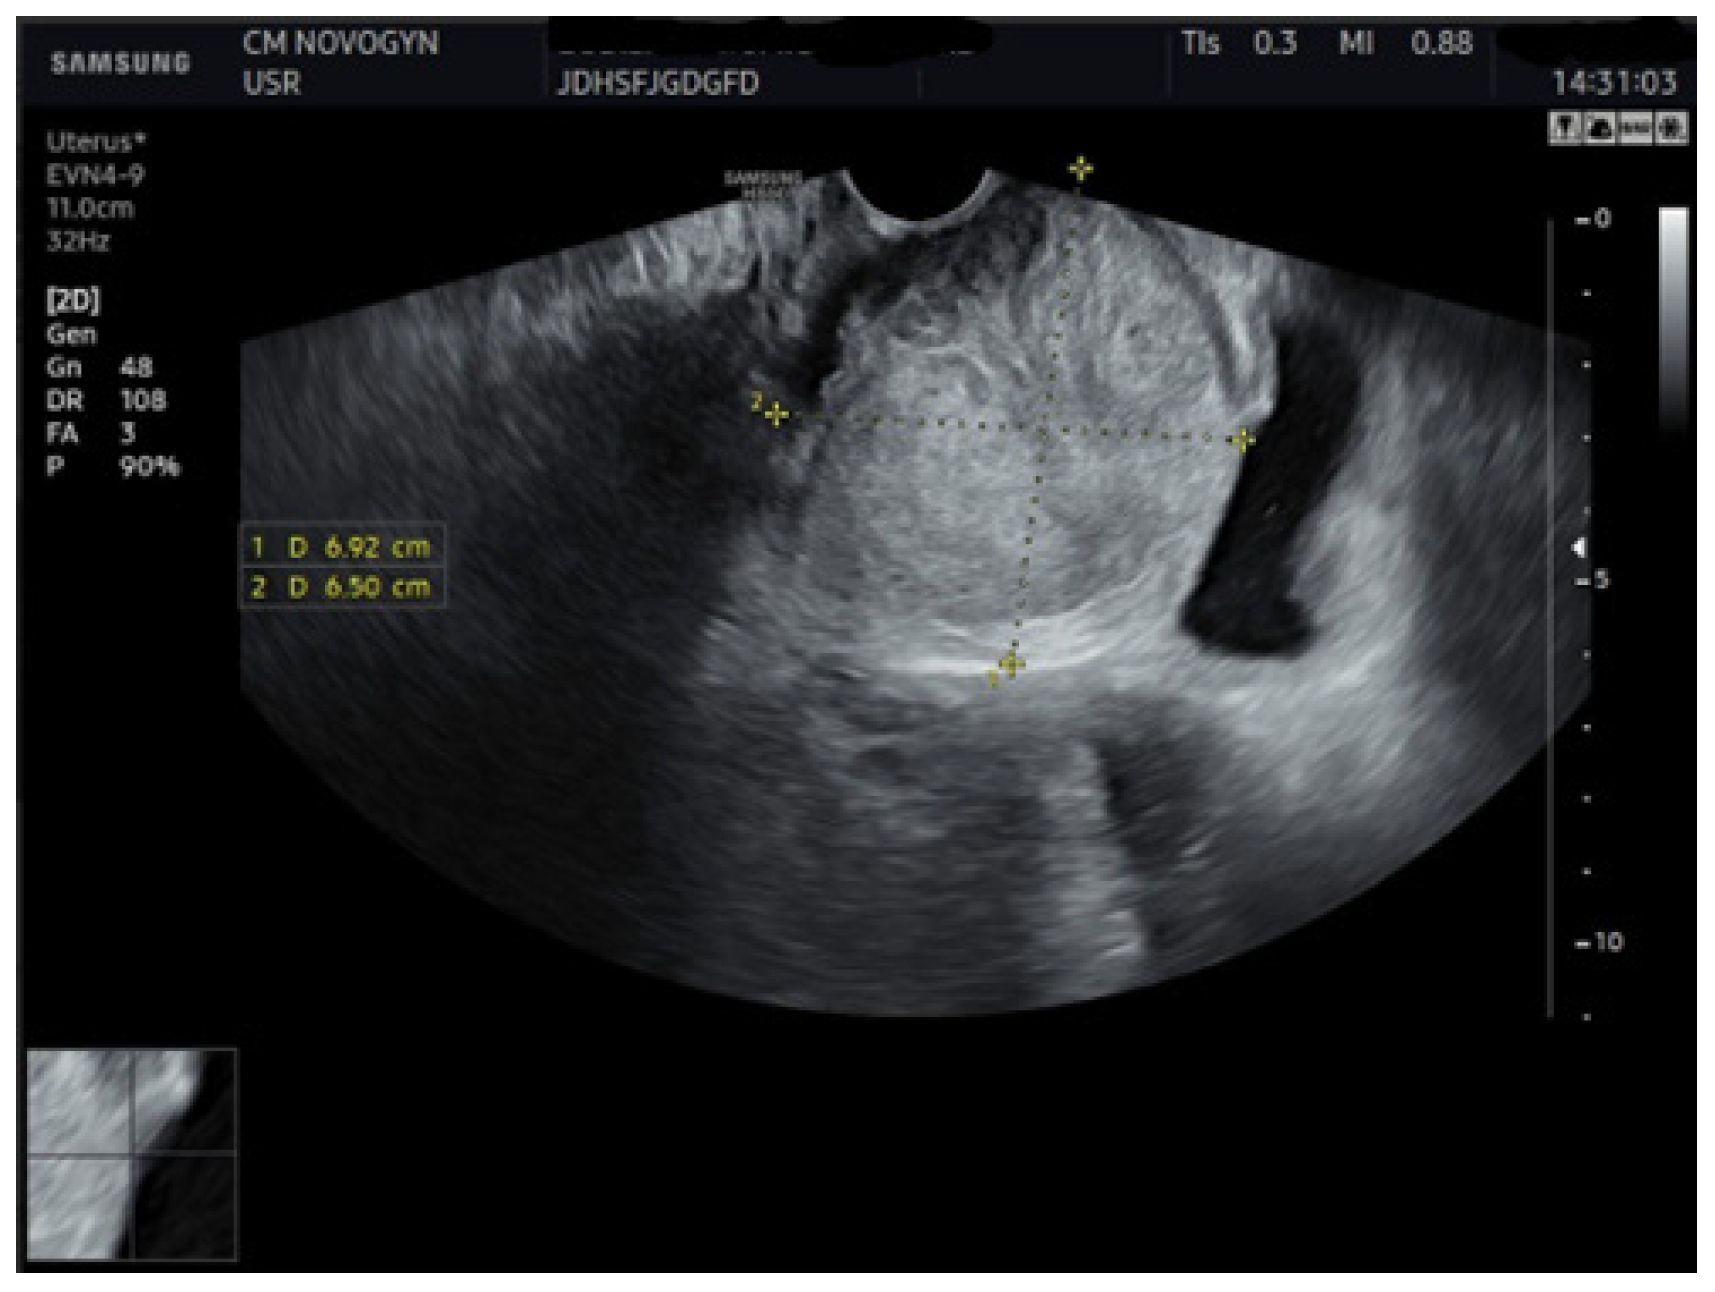

Initial transvaginal ultrasonography revealed a well-circumscribed, solid, predominantly hypoechoic mass measuring (6.9 × 6.5) cm located in the vesicovaginal region (Figure 1). The mass demonstrated homogeneous echotexture with well-defined borders and no internal cystic components. Color Doppler evaluation showed minimal internal vascularity. The uterus measured within normal limits, but demonstrated a fundal contour abnormality suggestive of septate uterus. Both ovaries appeared normal.

Additional abdominal ultrasonography confirmed a well-circumscribed mass measuring 6.07 × 6.10 cm from alternative imaging planes, demonstrating consistency with initial findings (Figure 2).

Figure 2.

Abdominal ultrasonographic image visualizing the well-demarcated, solid, hypoechoic mass (calipers) in the vesicovaginal region measuring (6.07 × 6.10) cm, confirming a consistent solid nature.